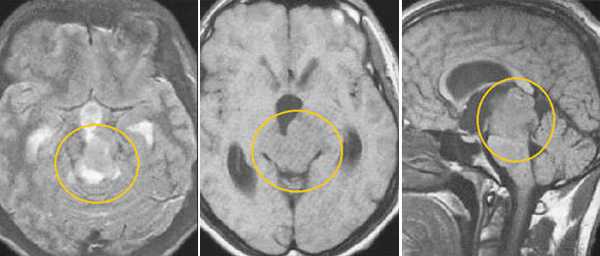

Пинеобластома. В режиме Т2 и Т1 выявляется опухоль задних отделов III желудочка мозга с развитием окклюзионной гидроцефалии. В строме опухоли небольшой участок подострого кровоизлияния. После в/в контрастирования опухоль интенсивно и достаточно гомогенно накапливает контрастирующее вещество.

Злокачественная смешанная герминативноклеточная опухоль. В боковых желудочках и пинеальной области определяются множественные опухолевые узлы с выраженным перитуморальным отеком. Внутрижелудочковые образования с признаками кровоизлияний. При в/в контрастировании определяется выраженное контрастирование узлов. Дополнительно визуализируется метастазирование по эпендиме боковых и IV желудочков мозга.

Глиобластома зрительного бугра справа. До и после в/в контрастирования определяется объемное образование с некротическим центром и контрастируемой периферической инфильтративной частью. Деформированы задние отделы III желудочка, начальный проявления окклюзионной гидроцефалии.